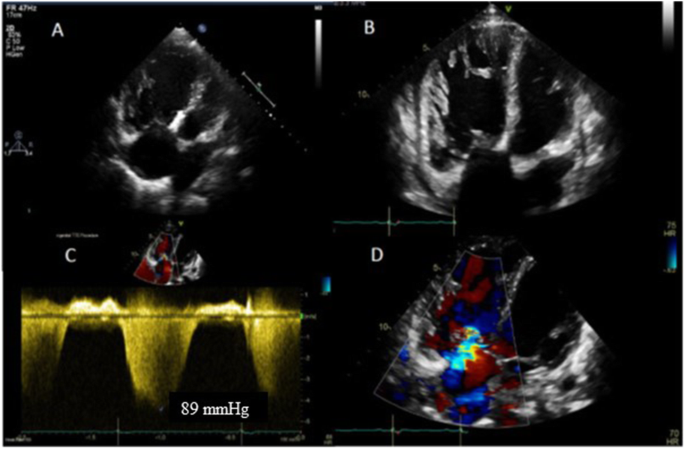

Echocardiogram during the late stages of pregnancy: In a and b, the right ventricle is severely dilated and forms the apex, with hypertrophy and preserved overall systolic function. The VSD closure device appears well seated in the peri-membranous region (arrow) with no obvious residual shunt. The right atrium is severely dilated. In c and d, there is moderate tricuspid regurgitation (multiple jets) with an estimated right ventricular systolic pressure of 89 mmHg plus right atrial pressure

She remained clinically stable for several years and at the age of 24 decided to pursue pregnancy, despite repeated counselling regarding the risks. The endothelin receptor antagonist was withdrawn, and she was commenced on sildenafil (a phosphodiesterase-5 inhibitor) and anticoagulation with therapeutic doses of enoxaparin sodium as soon as she became pregnant. She remained stable during the first half of her pregnancy, however, she presented at 23 weeks’ gestation with increasing shortness of breath and pre-syncopal episodes on moderate effort. She also developed small-volume haemoptysis related to a respiratory tract infection. She was admitted to the intensive care unit for advanced monitoring and was started on intravenous epoprostenol at slowly increasing doses up to 20 ng/kg/min (Figs. 2 and 3). She also required respiratory support with continuous positive airway pressure (CPAP) and high-flow oxygen, as well as antibiotics. She remained relatively stable and underwent uneventful elective Caesarean section at 32 weeks of pregnancy, having a healthy baby boy.